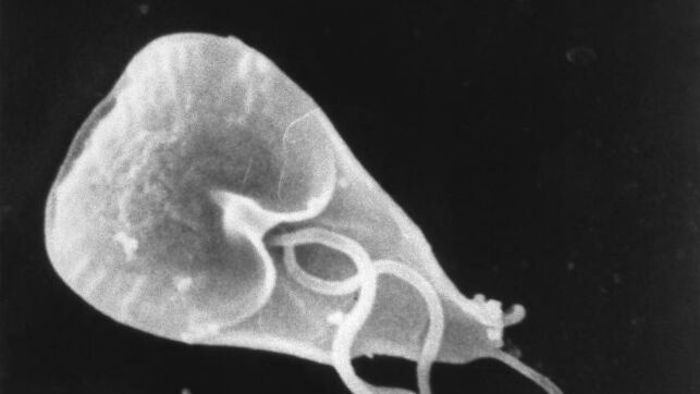

Los protozoos son diminutos organismos unicelulares que se multiplican dentro del cuerpo humano.

Por ejemplo, el protozoo Giardia tiene un ciclo de vida clásico de dos etapas. En la primera etapa, denominada trofozoíto, el parásito se dedica a nadar y consumir nutrientes del intestino delgado. En la segunda etapa se convierte en un quiste inmóvil.

Los quistes excretados en las heces pueden contaminar el suministro de agua, y la ingestión de alimentos o agua contaminados hace que se transmita el parásito. El contacto cercano entre personas y las condiciones de vida insalubres también pueden favorecer la transmisión.

La giardiosis puede conllevar síntomas como diarrea grave o crónica, cólicos abdominales, fatiga, debilitamiento y pérdida de peso, entre otros.